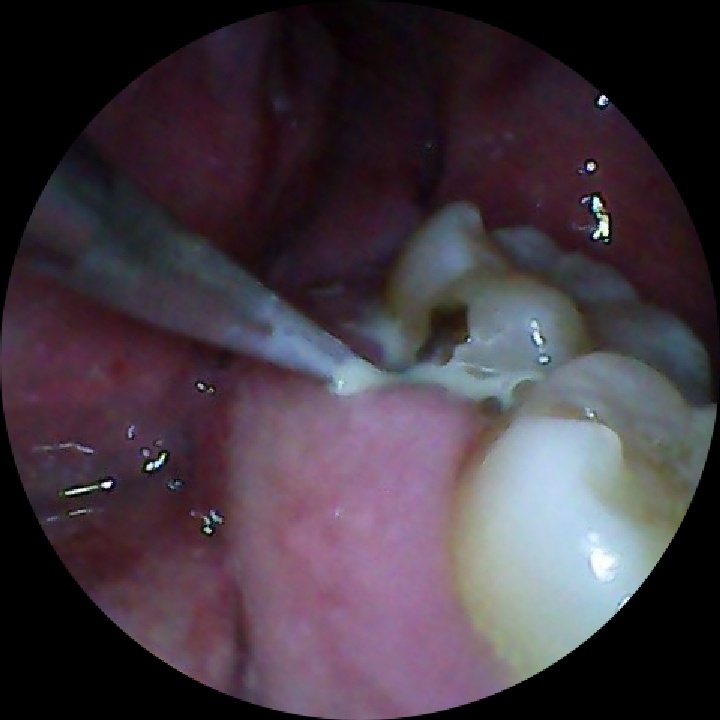

我之前自己发现智齿前一个牙齿横面中心有黑点。就专门跟牙医说了一下。一看是坏牙。把黑点磨掉,里面有扩散的龋齿。很可能是我以前拔智齿的时候不小心被工具打了一下,造成了一个裂纹。还好只是一个小坑。

之后检查又发现一个灯下黑。怀疑也是。顺着咀嚼面打了一个洞,发现里面确实是一个龋齿,而且坏的挺大。然后就是惨不忍睹的磨,我就感觉跟往我骨头里面钻骨髓一会的疼医生问我打麻药不。我说不用。没好意思问要不要钱,肯定是要钱的我就硬挺过来了。